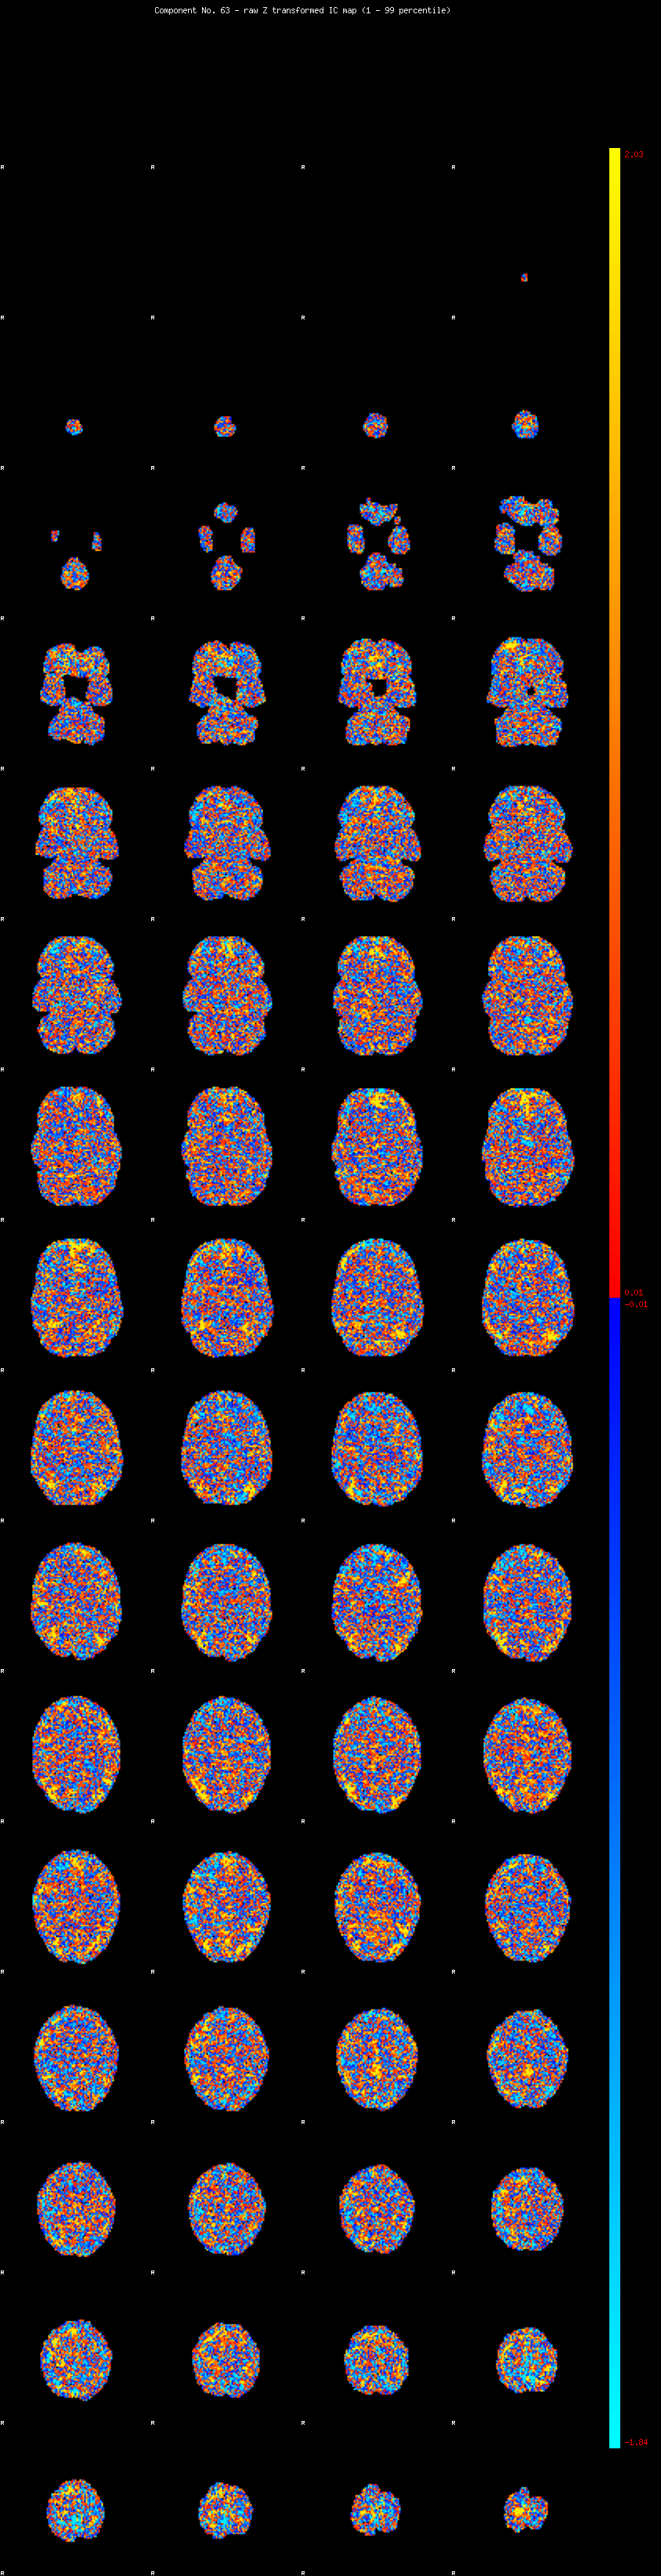

IC_63 Mixture Model fit

Means : -0.000000 2.329609 -2.384979

Vars : 1.000000 1.533915 0.715545

Prop. : 0.945492 0.039482 0.015027